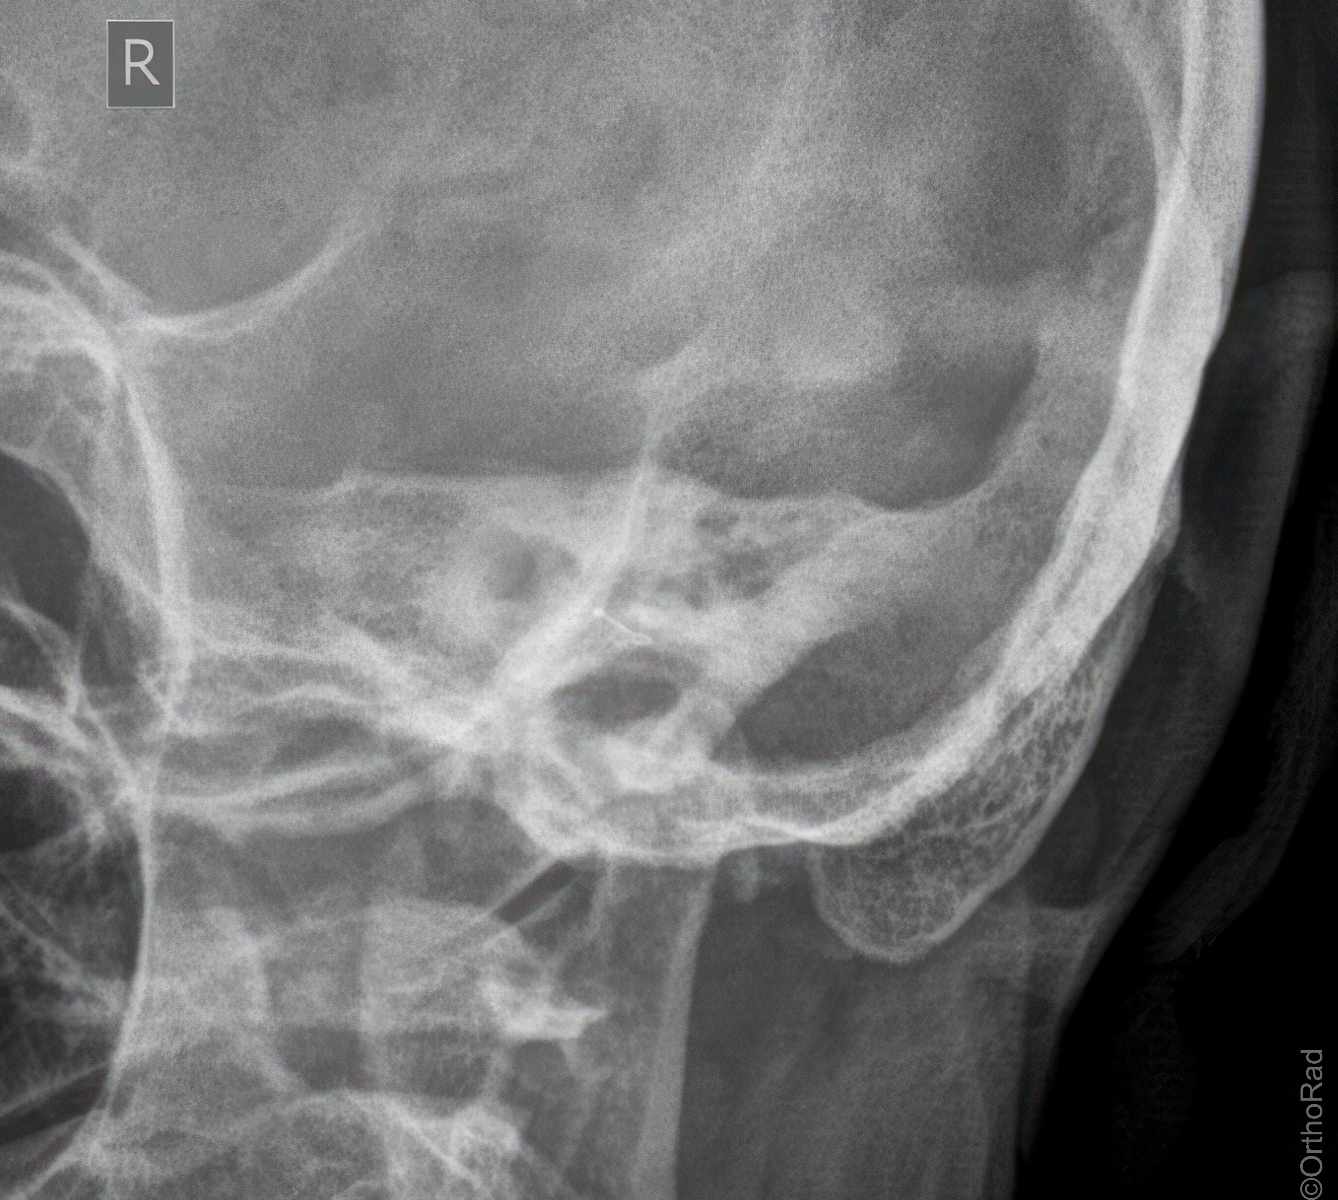

Kieferköpfchen nach Schüller

Technik

• FDA: 1,15 m

• Ausgangsformat: 18/18

• mit Raster

• Röhrenkippung: 20° cranio-caudal

Lagerung

Bauchlage, d.h. stabile Seitenlage, wie Schädel seitlich

zu untersuchende Seite aufliegend

Zentralstrahl

Zielt mit ca. 20° cranio-caudal auf das aufliegende Ohr (Zur Hilfe kann das detektorferne Ohr verwendet werden, welches auf die Platte projiziert wird.)

Qualitätskriterien

Freier Einblick auf das Kiefergelenk.